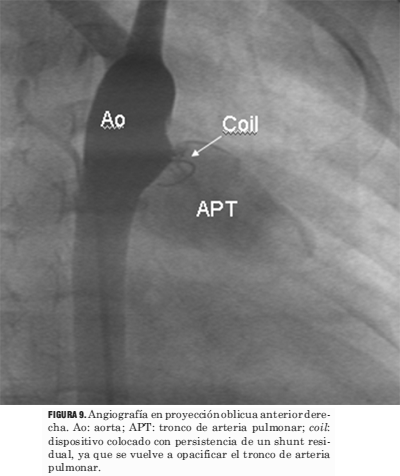

Los procedimientos de cierre del ductus se llevaron a cabo sin el uso simultáneo del ecocardiograma (figuras 9, 10, 11, 12 y 13).

Figura 9. Angiografía en proyección oblicua anterior derecha. Ao: aorta; APT: tronco de arteria pulmonar; coil: dispositivo colocado con persistencia de un shunt residual, ya que se vuelve a opacificar el tronco de arteria pulmonar.